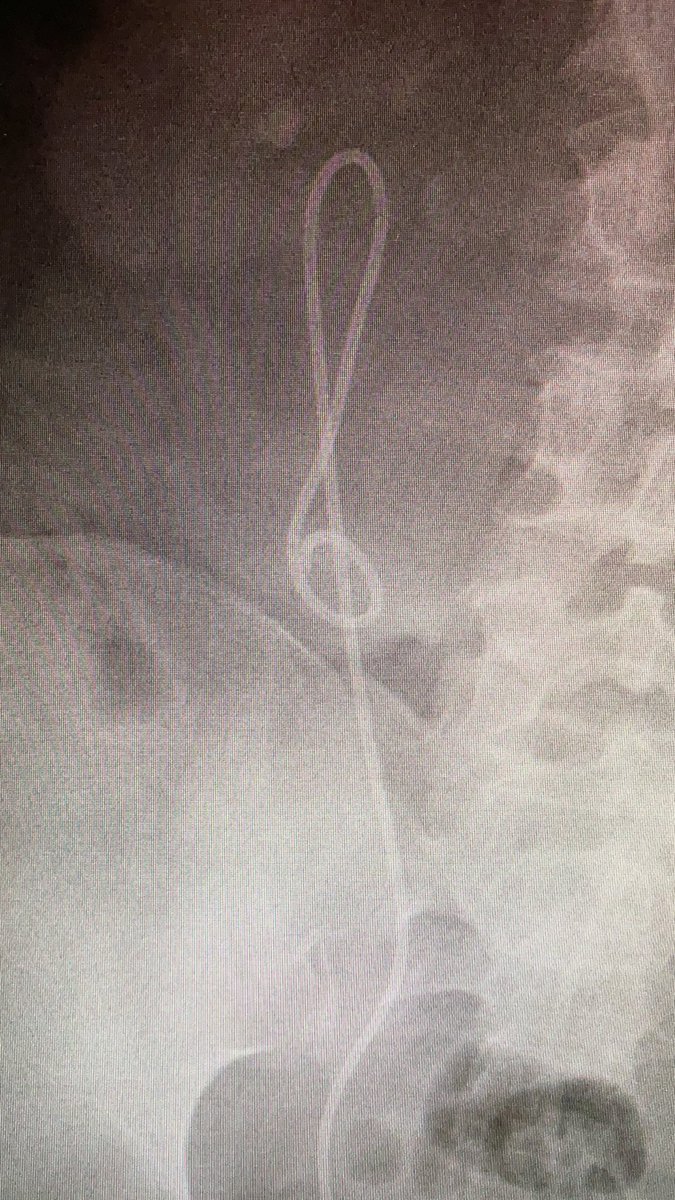

Catéter JJ que decide abandonar la urología para ser clave de sol.

Josep Balañà tweet media